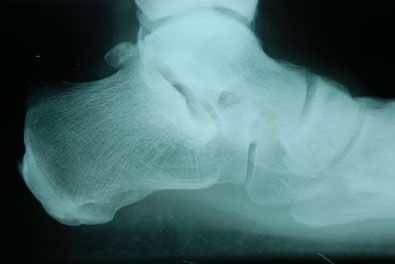

Occasionally, surgeons may perform posterior calcaneal osteototmy in addition to an isolated subtalar arthrodesis to provide additional translation of the posterior calcaneus.9 Another unique situation is depression of the posterior facet of the talocalcaneal joint after an intraarticular calcaneal fracture. Hindfoot realignment often requires restoration of heel height via bone block distraction arthrodesis of the talocalcaneal joint.10,11

Preoperative evaluation must include consideration of the goals of the procedure to fuse the talocalcaneal joint. The importance of alignment cannot be overemphasized. The fusion position of the calcaneus with respect to the talus dictates function for the remainder of the foot, especially the midtarsal joint.

If the surgeon uses the procedure for controlling a valgoplanus foot, the subtalar joint would be positioned with the lateral process of the talus up and out of the floor of the sinus tarsi in a more supinated position. If you are utilizing the procedure to correct an over-supinated hindfoot, the opposite would be the case for positioning of the fusion. In the case of a fusion for a previous calcaneus fracture, the surgeon would be elevating the depressed posterior facet by an interpositional bone graft to restore a more anatomic relationship between the talus and calcaneus for the most functional fusion.10,11